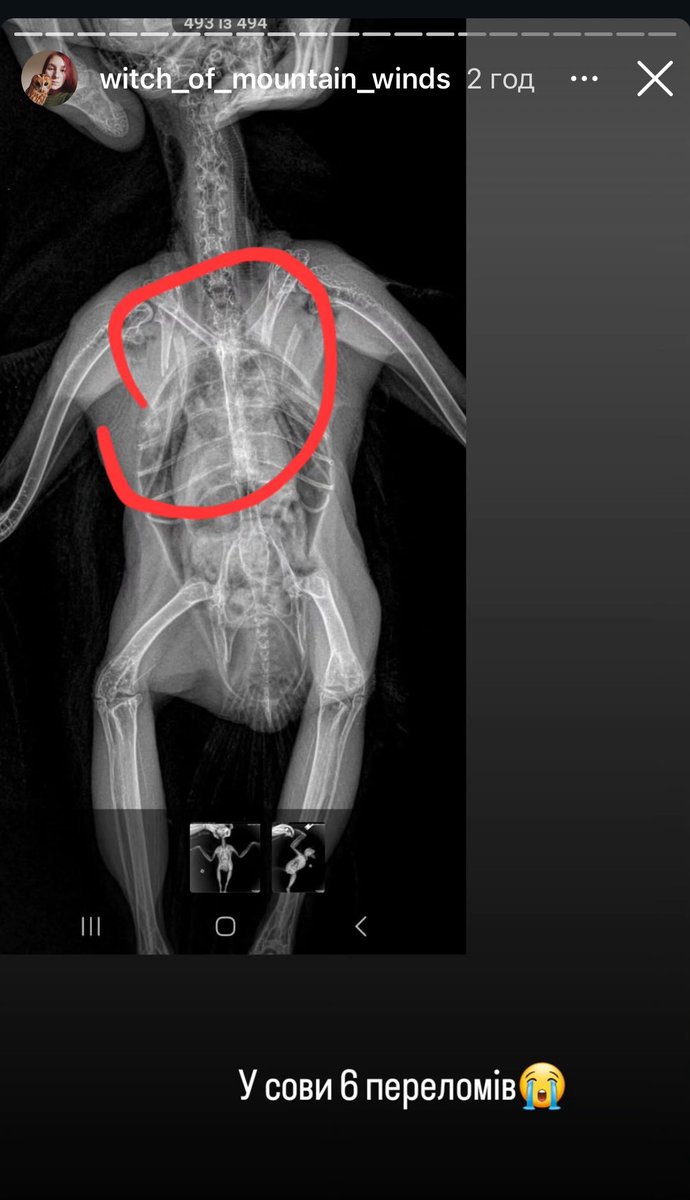

Вет клініка у Вінниці, яка регулярно гробить тварин. Вже писала про них раніше, і от чергова історія. Не знаю наскільки криворуким «спеціалістом» треба бути, щоб не побачити ШІСТЬ МАТЬЙОГОВЙОБ ПЕРЕЛОМІВ 🤬 «Всьо ок, можна випускать в природу» 🤡